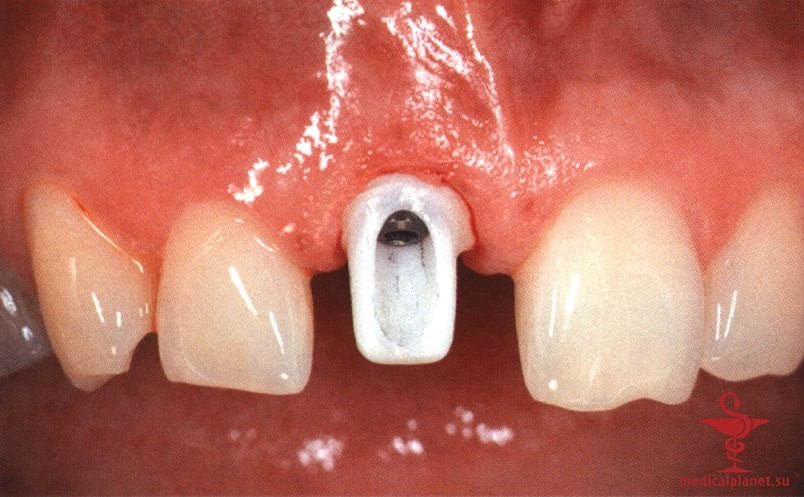

в) Отслаивание лоскута при одноэтапной имплантации. Одноэтапная немедленная имплантация кажется предпочтительной, поскольку герметичное ушивание раны сразу после удаления зуба представляется нецелесообразным. Вместо плотного сопоставления краев раны на имплантат немедленно фиксируют формирователь десны или временную реставрацию, что снижает риск деформации прилегающих мягких тканей.

Следует помнить, что любой, даже самый маленький лоскут требует наложения швов в области сосочков, а каждый разрез в этой зоне ведет к уменьшению их высоты, как обсуждалось в отдельной статье на сайте (просим Вас пользоваться формой поиска по сайту выше) (рис. 3). Иными словами, при немедленной имплантации в эстетически значимой зоне нужно избегать отслаивания лоскута.